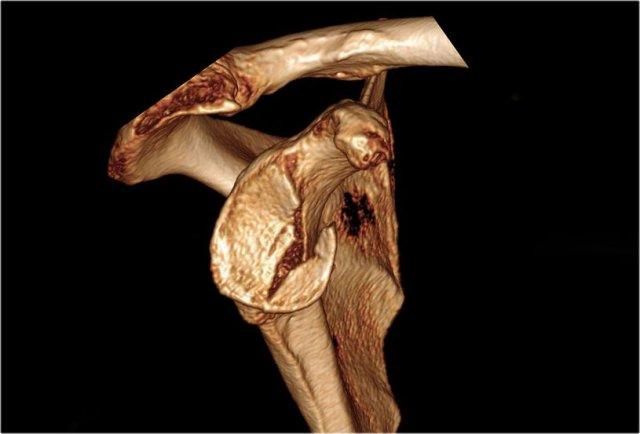

Tái tạo 3D của tổn thương Bankart xương lớn tại vị trí 2 – 6 giờ.